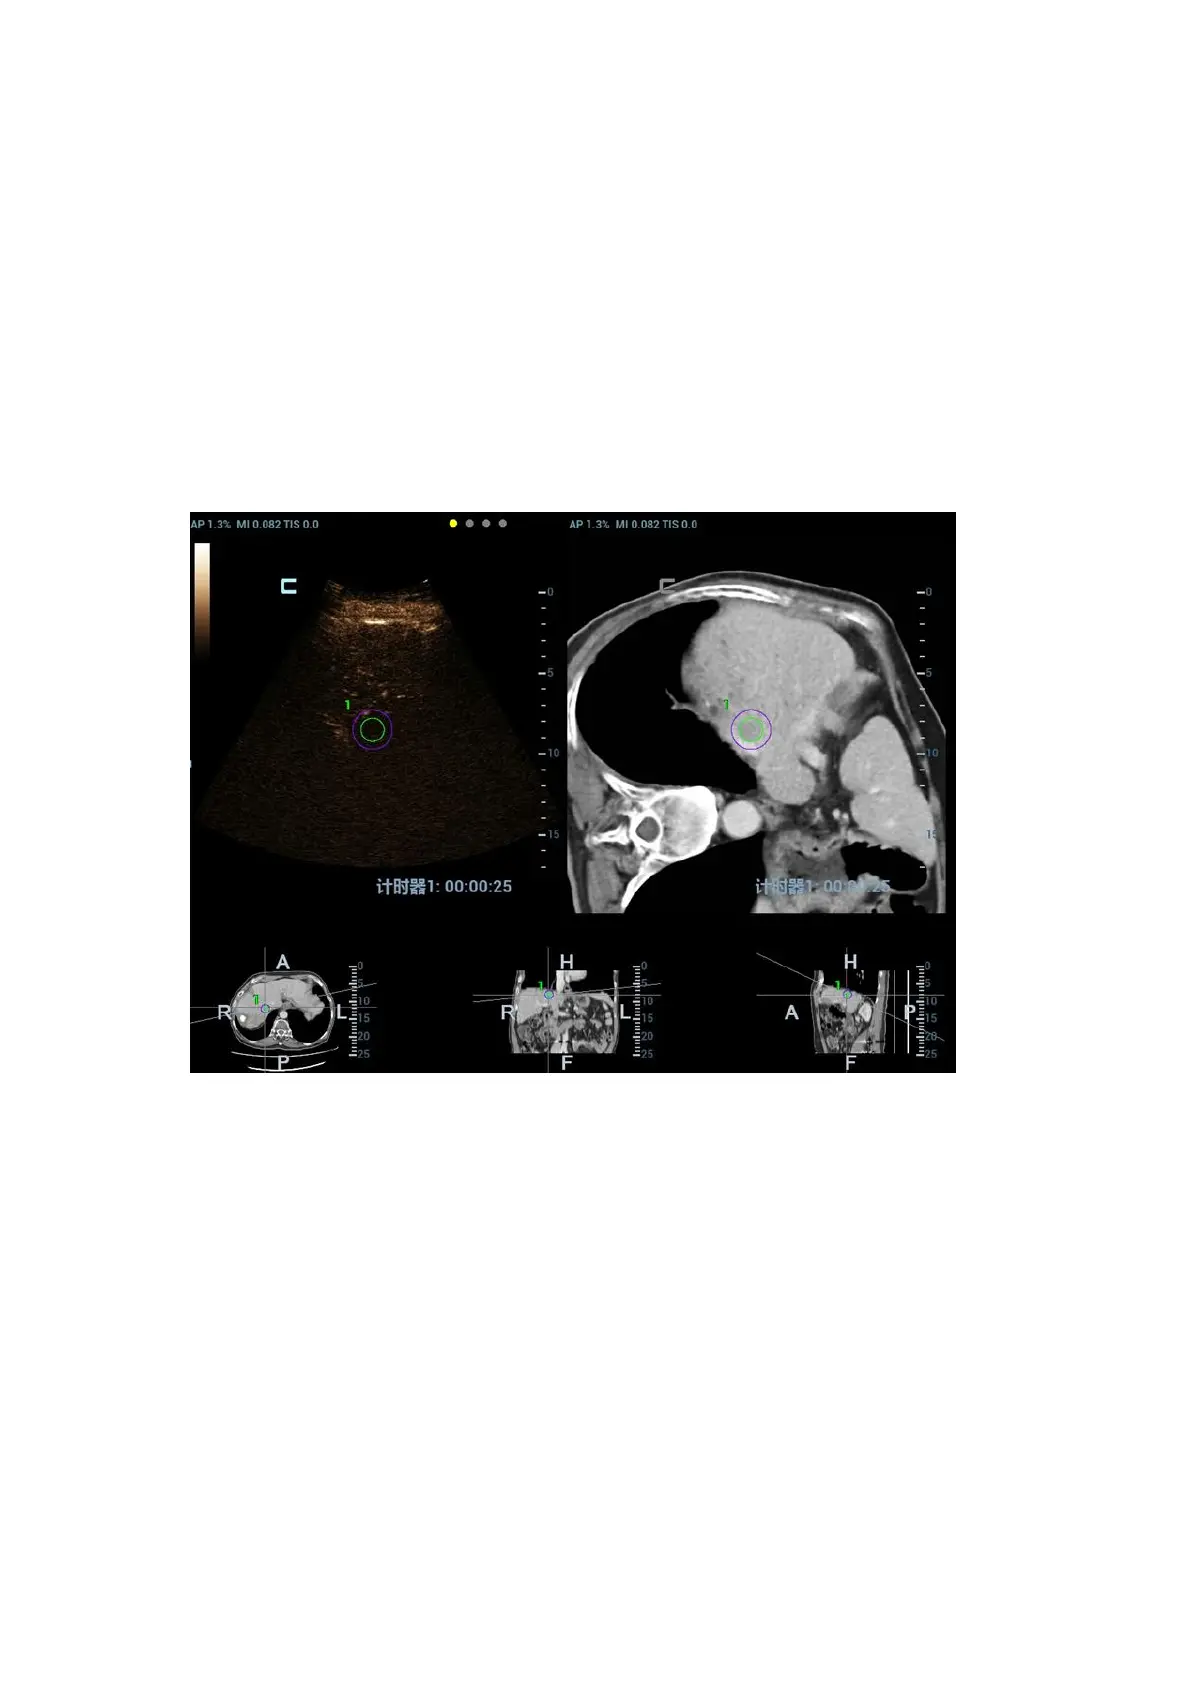

5.16.8 Contrast Fusion Imaging

Contrast Fusion Imaging increases the possibility of diagnosing the difficult lesions in the pre-

operation; improves the accuracy to ablating the lesion in the intra-operation; estimates the

therapeutic effect of the target in the post-operation.

2. Contrast Fusion Dual Live:

Select [Contrast][Dual Live] to adjust the fusion ratio. Adjust the display ratio that tissue

image registers with CT/MR image (see Window 1 and window 2). Adjust the display ratio that

contrast image registers with CT/MR image (see window 3 and window 4).